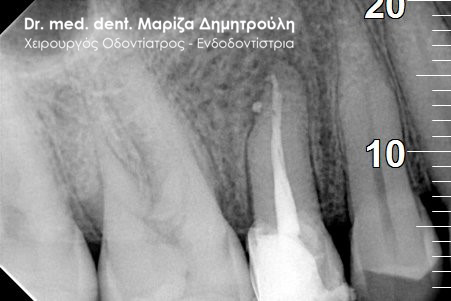

Η ασθενής περιγράφει έναν έντονο συνεχόμενο πόνο στη δεξιά πλευρά της άνω γνάθου που δεν την αφήνει τις τελευταίες μέρες μα εργαστεί. Μετά την κλινική και ακτινογραφική εξέταση της περιοχής διαπιστώθηκε οτι το υπαίτιο δόντι για την πρόκληση των έντονων συμπτωμάτων ήταν ο δεύτερος δεξιός άνω γομφίος, ο οποίος διέθετε ένα παλιό βαθύ σφράγισμα που πίεζε το νεύρο του δοντιού.

Μετά τη χορήγηση τοπικής αναισθησίας αφαιρέθηκε το παλιό σφράγισμα και εντοπίστηκαν οι ριζικοί σωλήνες του δοντιού (βλέπε φωτογραφία). Μετά την κατάλληλη επεξεργασία των ριζικών σωλήνων και εφόσον το δόντι ήταν ασυμπτωματικό η απονεύρωση ολοκληρώθηκε με την έμφραξη των ριζικών σωλήνων με ειδικό εμφρακτικό υλικό.

ΠΡΙΝ